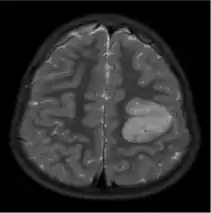

MRI scan of a four-year-old boy with AG. The light grey part indicated a hyperintense and elastic lesion in his left posterior frontal lobe.[12]

The neurological features of AG tumors are visible via CT scanning or MRI. A clear indication of AG may appear as well-delineated, solid, T2-hyperintense, non-enhancing cortical lesions located in the temporal or frontal lobes in MRI.[1] Another diagnostic trait is a stalk-like extension to adjacent brain ventricles.[13] These traits are similar to low-grade gliomas from a radiological perspective.

The results from CT scanning and MRI are different in terms of clarity and effectiveness of diagnosis. AG displays an expansive non-enhancing cortical tumor in CT scanning, whereas MRI shows a relatively clearer appearance of AG and the tumors appear to be infiltrative, well-defined, and hypointense with T1 lesion.[4] T2/FLAIR lesions indicate AG as a tumor tissue with some extension toward the ventricles along vessels.[4] The possibility of cystic-appearing areas exists as well. In some cases, MRI results show an increase in ribbon-like signal on T1W1 lesions.[4] The clear radiographic outcomes of MRI makes it the more widely used option in the diagnosis of AG.[4]